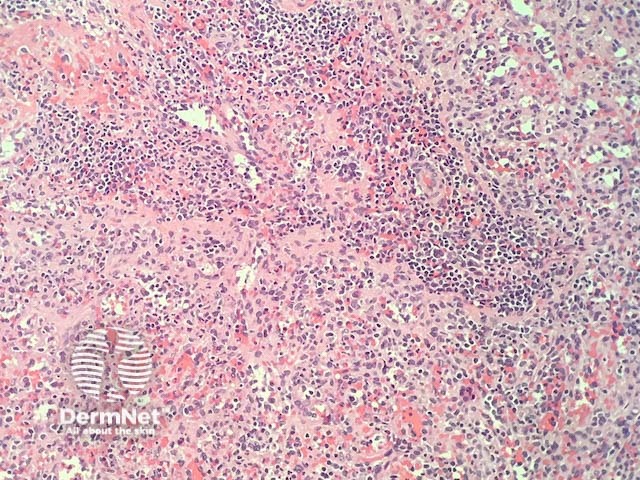

In splenosis, the histopathology shows normal splenic tissue, usually located in the subcutis (figures 1, 2). Spleen can be recognised by the presence of red pulp (composed of venous sinusoids allowing passing of red blood cells) and white pulp (composed of sheaths of lymphoid cells around arteries).

Figure 1

Figure 2